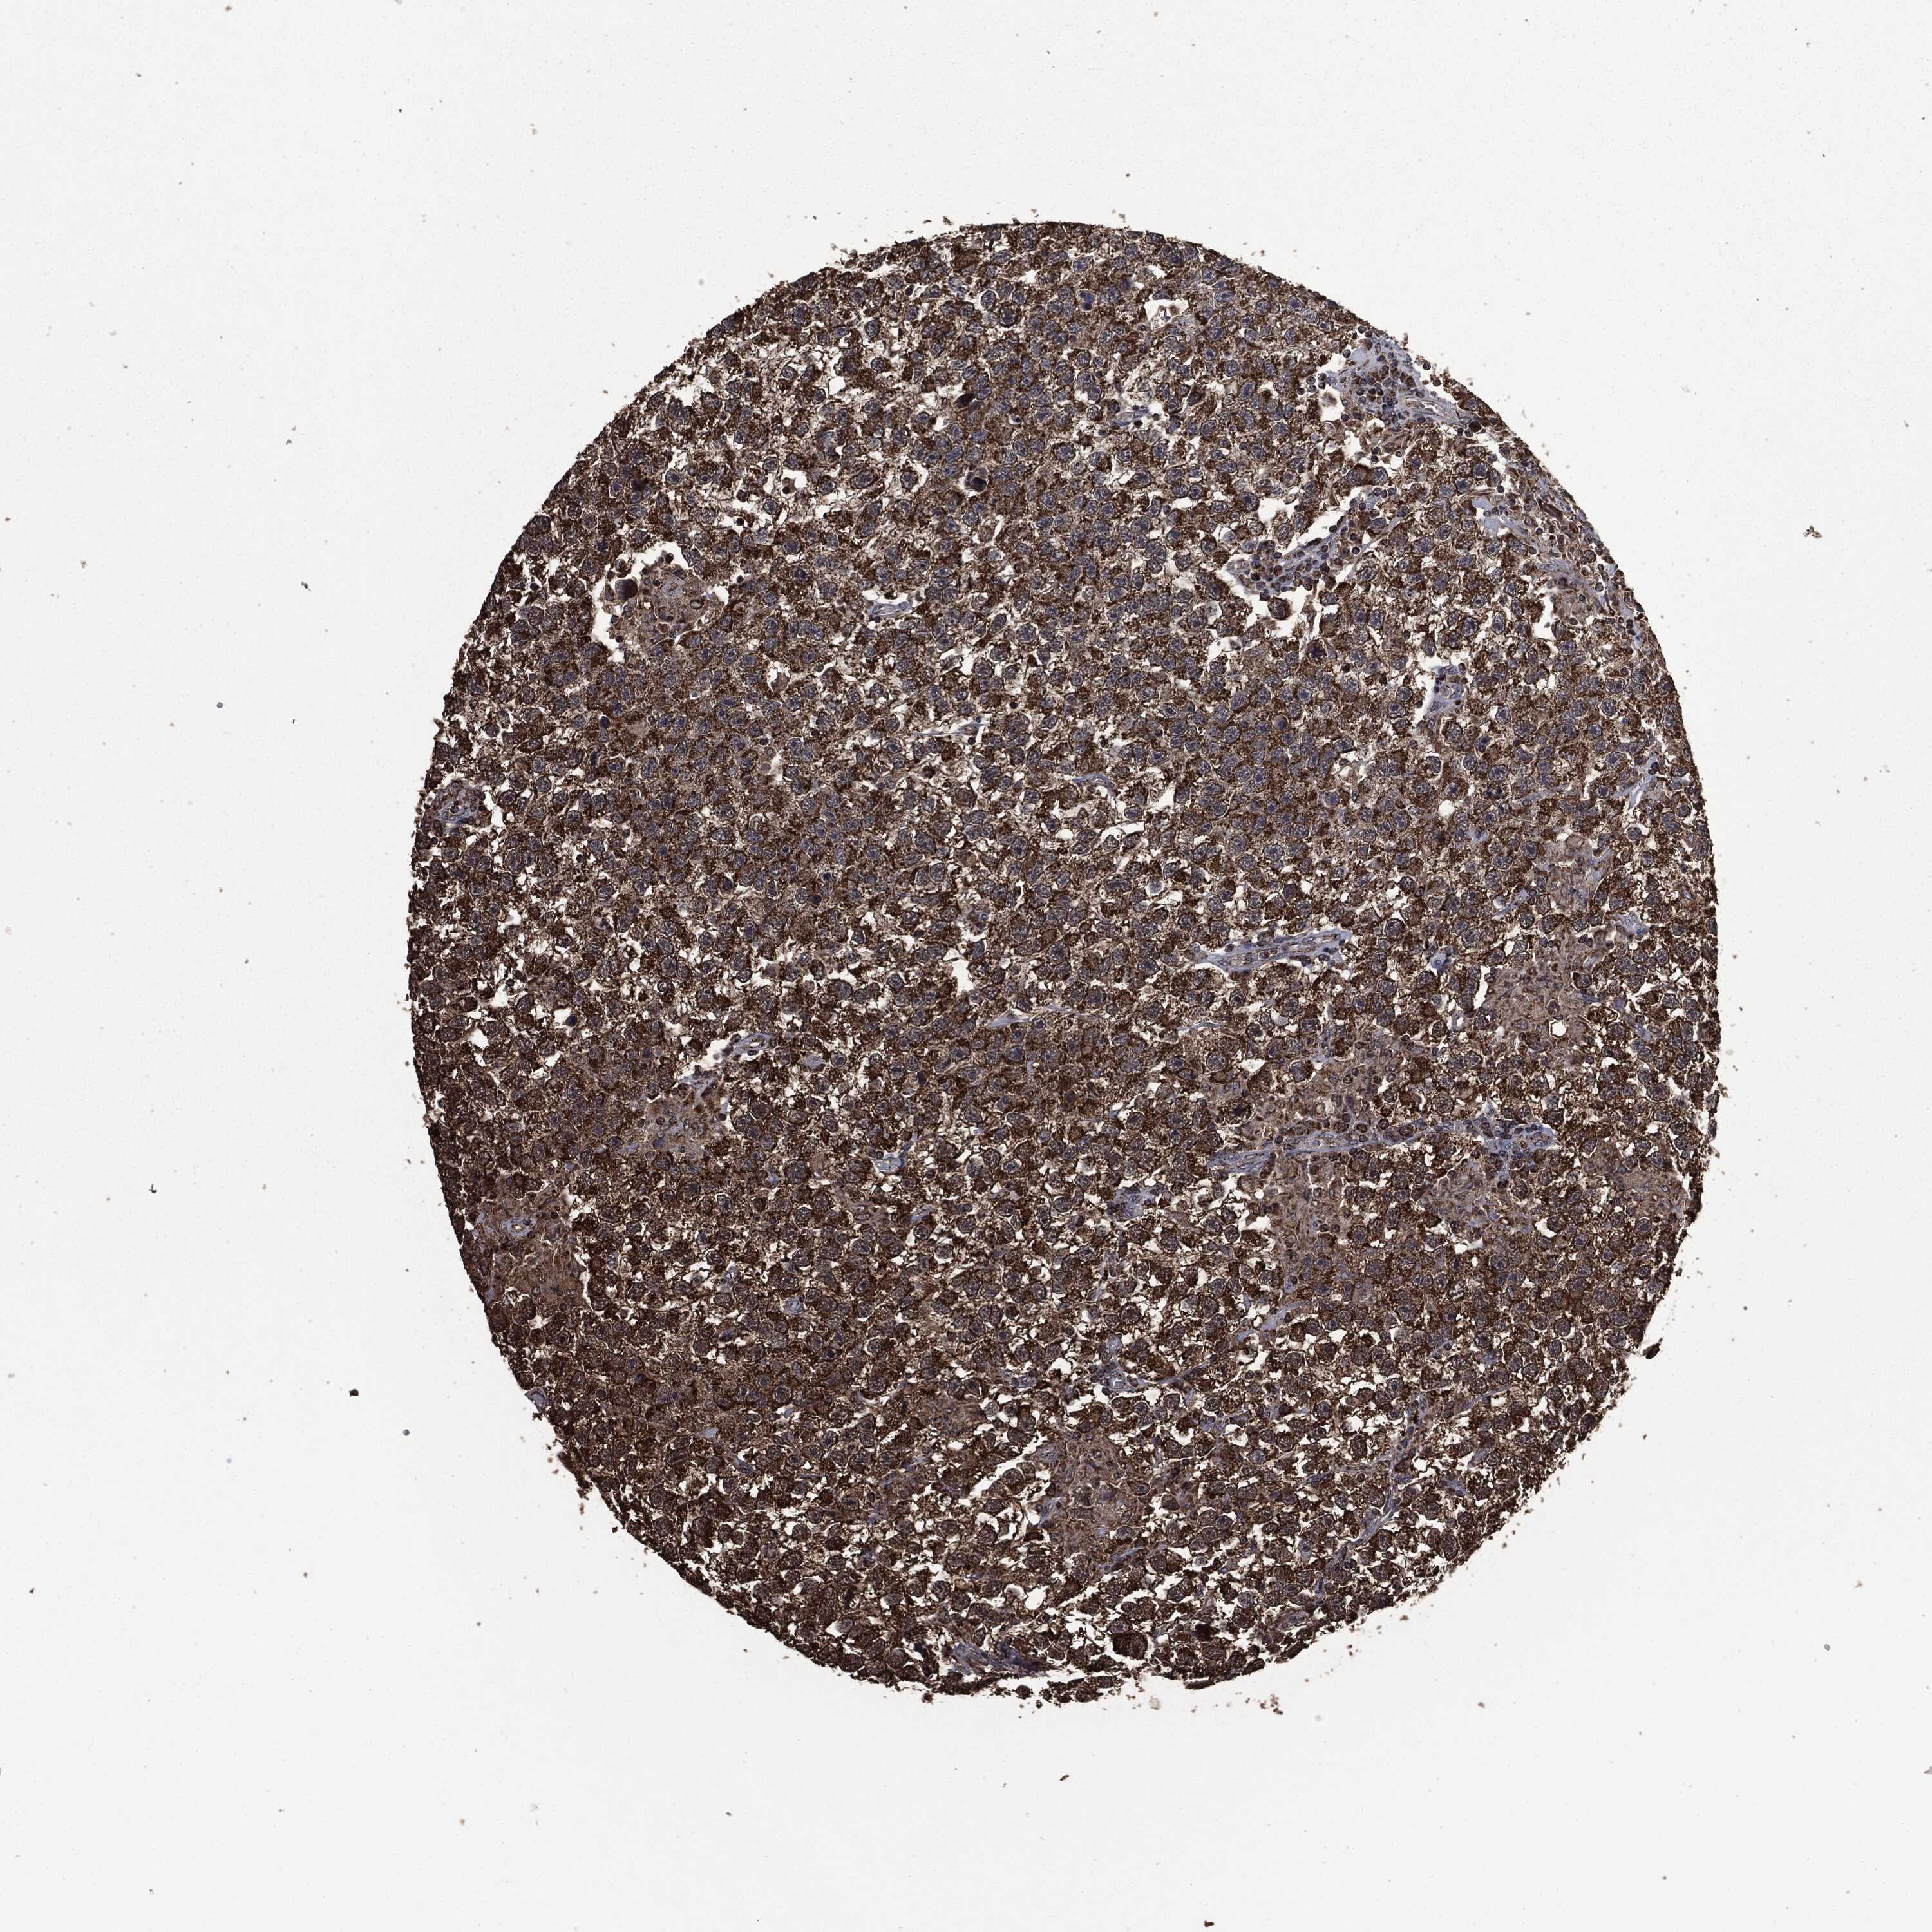

Antibody HPA006723

Antibody CAB080348

Staining

High

Medium

Low

Not detected

Intensity

Strong

Moderate

Weak

Negative

Quantity

>75%

75%-25%

<25%

None

Location

Carcinoma, Embryonal, NOS

Seminoma, NOS

TESTIS CANCER - Protein expressioni

A mouse-over function shows sample information and annotation data. Click on an image to view it in a full screen mode. Samples can be filtered based on level of antibody staining by selecting one or several of the following categories: high, medium, low and not detected. The assay and annotation is described here.

Note that samples used for immunohistochemistry by the Human Protein Atlas do not correspond to samples in the TCGA dataset.

Antibody stainingi

Antibody staining in the annotated cell types in the current human tissue is reported as not detected, low, medium, or high, based on conventional immunohistochemistry profiling in selected tissues. This score is based on the combination of the staining intensity and fraction of stained cells.

Each image is clickable and will lead to virtual microscopy that enables deeper exploration of all samples and also displays staining intensity scores, fraction scores and subcellular localization as well as patient and tissue information for each sample.